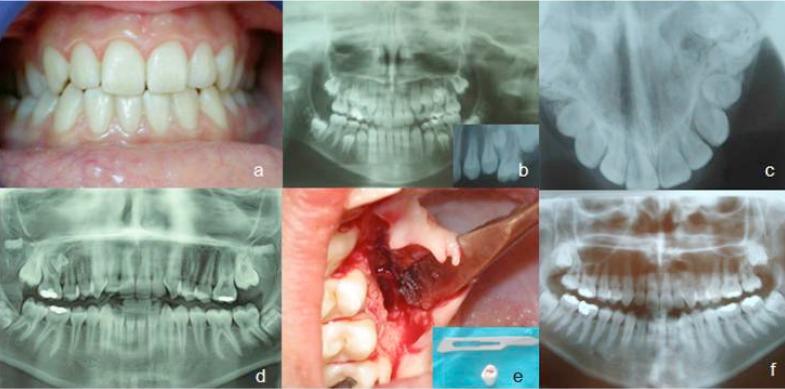

The presence of supernumerary teeth, also known as hyperdontia, is the condition of having teeth in addition to the regular number of teeth. The occurrence of multiple supernumerary teeth is often found in association with syndromes such as Gardner syndrome, Anderson-Fabry disease, Ellis-van Creveld syndrome, Ehlers-Danlos syndrome, incontinentia pigmenti, and Tricho-rhino-phalangeal syndrome. Only a few examples of nonsyndromic multiple supernumerary teeth have been reported in literature. In this report, we present the unusual case and 9-year follow up of a non-syndrome female patient with bilateral supernumerary teeth that occurred with an interval of several years.

额外牙的存在,也称为多生牙,是指牙齿数量超出正常数量的情况。多颗额外牙的出现常与诸如加德纳综合征、安德森 - 法布里病、埃利斯 - 范克里维尔德综合征、埃勒斯 - 当洛综合征、色素失禁症和毛发 - 鼻 - 指综合征等综合征相关。文献中仅报道了少数非综合征性多颗额外牙的病例。在本报告中,我们呈现了一例非综合征女性患者双侧额外牙的罕见病例及其9年随访情况,双侧额外牙的出现间隔数年。